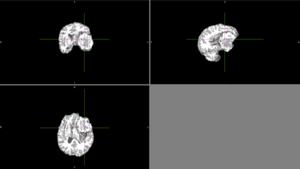

Semi-automatic segmentation with Slicer was relatively successful. Sometimes the segmentation would bleed outside of the tumor into voxels with similar intensities.